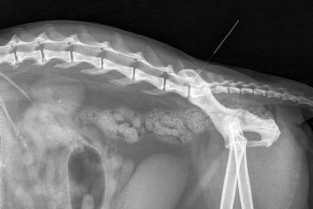

L’acupuncteur vétérinaire fait souvent ses gammes sur le Dos. De la simple lombalgie à l’urgente hernie discale, l’acupuncture prouve au quotidien son précieux apport complémentaire en traitement tout comme en diagnostic. Ces conférences destinées aux praticiens référents comme aux praticiens juste initiés vous permettront de faire...le point.